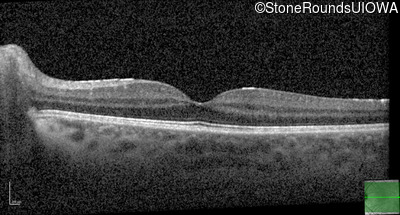

Optical Coherence Tomography - Left - 20/20 -1

Exemplar / OCT Stack